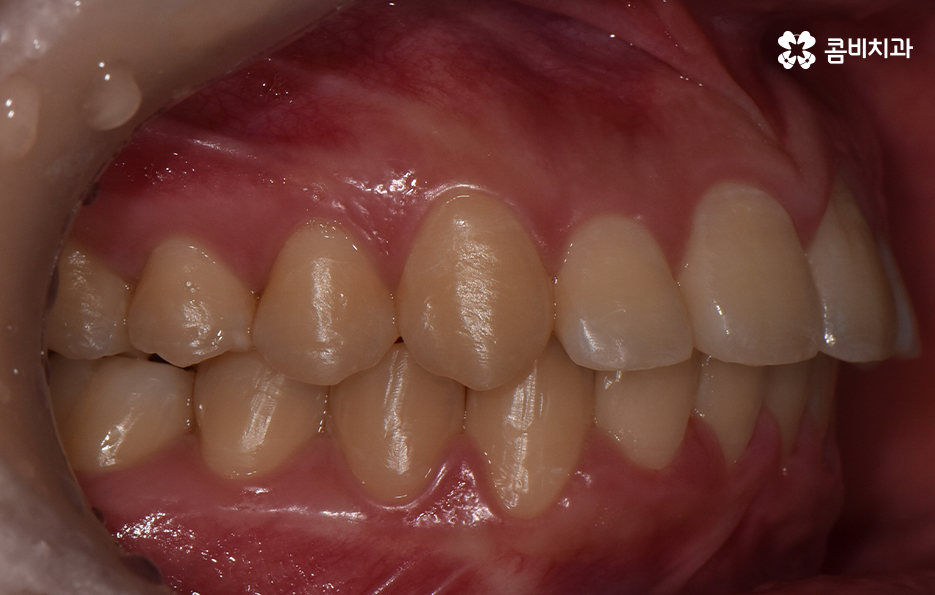

오늘 덧니 비발치 교정 사례로 보시는 환자분의 경우에는 윗니와 아랫니 앞니 부분에 조금씩 덧니가 있는 상태로 덧니를 제외하면 대체적으로 치열 상태는 고른 편이며 덧니 교정 사례 중에서는 돌출입도 함께 개선해야 하는 경우가 많지만 위 환자분의 경우에는 돌출입의 정도가 양호했고 입술라인 역시도 정상 범위에 가까웠기 때문에 발치를 필요로 하지 않았지만 치아의 이동 공간과 보다 자연스러운 입술라인 그리고 얼굴형과의 조화를 고려하여 악궁 확장과 어금니 후방 이동을 적절히 활용하여 교정 치료가 진행되었다고 볼 수 있어요

치아교정 기간은 개인차가 워낙 크기 때문에 교정에 대한 예상 기간을 치과 방문 없이 예측하기란 어렵기 때문에 정확하게 예상하려면 치과에 방문하는 것이 좋겠지만 보편적으로 말씀드리자면 치아가 이동해야 하는 이동량과 정도에 따라서 차이가 커진다고 볼 수 있어요. 예를 들어 발치교정에 비해 오늘 소개드린 덧니 비발치 교정이 치아의 이동이 필요한 정도가 적기 때문에 치료 기간 역시도 비교적 짧은 편이라고 할 수 있으며 오늘 소개 드린 케이스의 경우 약 1년 3개월 정도만에 치료가 마무리될 수 있었어요

정리하면 오늘 소개드린 덧니 비발치 교정 사례의 경우 기본적으로 덧니의 정도나 전체 치열의 상태가 대체적으로 양호한 편이기도 했지만 얼굴형이나 골격적인 부분, 입술라인으로 볼 때도 덧니 교정 사례에서 자주 보이는 돌출입의 개선에 대한 니즈가 큰 편은 아니었기 때문에 비발치 교정으로 충분히 치료가 가능했고 발치를 해서도 안되는 케이스에 속했어요. 아무래도 덧니 교정하면 발치 교정 케이스가 많다보니 겁부터 내시는 분들도 많긴 하지만 덧니 교정 사례도 워낙 다양한 사례가 많기 때문에 자신에게 적합한 치료 계획을 치과 검진을 통해 교정 전문의와 충분히 상의하신 다음에 좋은 판단 내리시길 바라고 있어요